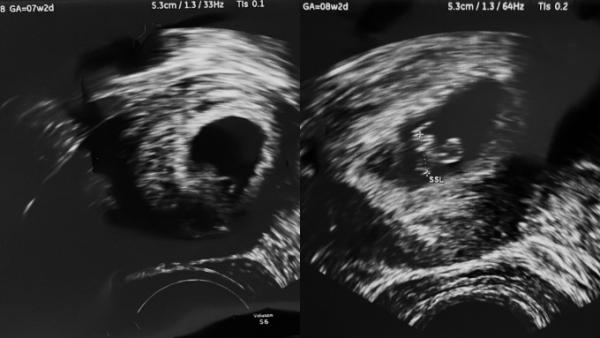

Das war bei mir genau so. In der 7. Woche war auch noch nichts zu sehen. Eine Woche später dann schon ein kleiner Mensch. Ärztin nannte sie einen Eckenhocker Siehe Foto. Das ist auch meine erste Schwangerschaft und ich habe mir viel Sorgen gemacht. Ich kann dich aber beruhigen. Es ist bestimmt alles gut ![]()